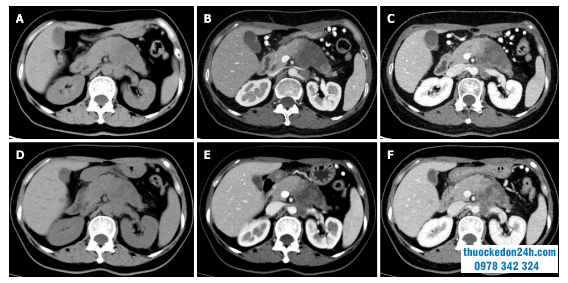

Multidetector CT (MDCT) là phương pháp hình ảnh được sử dụng thường xuyên nhất để đánh giá phản ứng của ung thư biểu mô tuyến ống tụy sau điều trị bổ trợ tân sinh. So với các kỹ thuật hình ảnh khác, ưu điểm của nó bao gồm độ phân giải không gian cao hơn và khả năng tái tạo đa phương diện. Tuy nhiên, các nghiên cứu gần đây đã chỉ ra rằng hiệu quả chẩn đoán của MDCT trong việc đánh giá khả năng cắt bỏ khối u và tái phân bố các khối u ở ranh giới là không khả quan. Trong một nghiên cứu trên 129 bệnh nhân có ung thư biểu mô tuyến tụy ở ranh giới phẫu thuật triệt căn, các tác giả nhận thấy rằng các tiêu chí đánh giá đáp ứng thường được sử dụng trong các tiêu chí về khối u đặc (RECIST) không phù hợp để đánh giá đáp ứng của khối u sau điều trị bổ trợ tân sinh, vì có rất ít thay đổi hình thái trên hình ảnh sau điều trị. Một tổng quan hệ thống báo cáo rằng chỉ một số ít bệnh nhân cho thấy khối u nhỉ lại sau điều trị bổ trợ tân sinh và hầu hết bệnh nhân (53% -80%) có bệnh ổn định. Các kết quả tương tự cũng được báo cáo bởi một nghiên cứu gần đây cho thấy rằng việc đánh giá khả năng cắt bỏ được của MDCT sau điều trị bổ trợ tân sinh tương đối không nhạy cảm và không đặc hiệu để dự đoán cắt bỏ R0, bởi vì MDCT không thể phân biệt chính xác giữa khối u còn sót lại và sẹo mô sau khi khối u thoái triển. Hơn nữa, viêm tụy cấp do viêm cục bộ cũng không thể phân biệt được với sự thâm nhiễm của khối u và vùng thâm nhiễm của khối u được thay thế bằng mô sợi, điều này không dẫn đến những thay đổi rõ ràng về kích thước khối u. Tất cả những yếu tố này dẫn đến việc đánh giá thấp khả năng cắt bỏ khối u.Gần đây, một số nghiên cứu đã bắt đầu khám phá xem liệu các đặc điểm hình ảnh khác với kích thước khối u và sự tăng cường trên hình ảnh MDCT có thể được sử dụng để đánh giá phản ứng của khối u trong ung thư biểu mô tuyến ống tụy hay không. Một nghiên cứu của Cassinotto và cộng sự đã chỉ ra rằng sự hồi quy một phần của tiếp xúc khối u với mạch máu sau điều trị bổ trợ tân sinh cho thấy sự phù hợp để thăm dò phẫu thuật, bất kể sự giảm kích thước khối u hoặc sự tham gia của mạch máu còn lại. Một nghiên cứu khác của Amer và cộng sự cho rằng những thay đổi ở giao diện ung thư biểu mô tuyến ống tụy / nhu mô có thể được sử dụng như một yếu tố dự báo sớm về phản ứng với điều trị bổ trợ tân sinh . Một nghiên cứu gần đây từ Wei và cộng sự cho thấy đường kính khối u lớn nhất và thể tích khối u phóng xạ trên MDCT sau điều trị có liên quan đến giai đoạn khối u bệnh lý và phản ứng của khối u với điều trị bổ trợ tân sinh. Mặc dù MDCT có độ phân giải cao trong việc hiển thị các đặc điểm hình thái của khối u và các cấu trúc mạch máu xung quanh, nhưng nó có độ đặc hiệu thấp do thiếu sự giảm khối u rõ ràng sau điều trị bổ trợ tân sinh trong ung thư biểu mô tuyến tụy, cũng như sự hiện diện của mô xơ và viêm tụy cục bộ. Do đó, MDCT có độ đặc hiệu và độ nhạy thấp trong việc phục hồi ung thư biểu mô tuyến ống tụy sau điều trị bổ trợ tân sinh. Tuy nhiên, việc định lượng và đánh giá thêm các chỉ số hình ảnh trên ảnh MDCT có thể cải thiện đáng kể việc đánh giá đáp ứng của khối u và giá trị tiên lượng của bệnh nhân ung thư biểu mô tuyến ống tụy sau điều trị bổ trợ tân sinh .

Đánh giá đáp ứng với chụp cắt lớp vi tính tăng cường cản quang sau khi điều trị bổ trợ tân sinh.